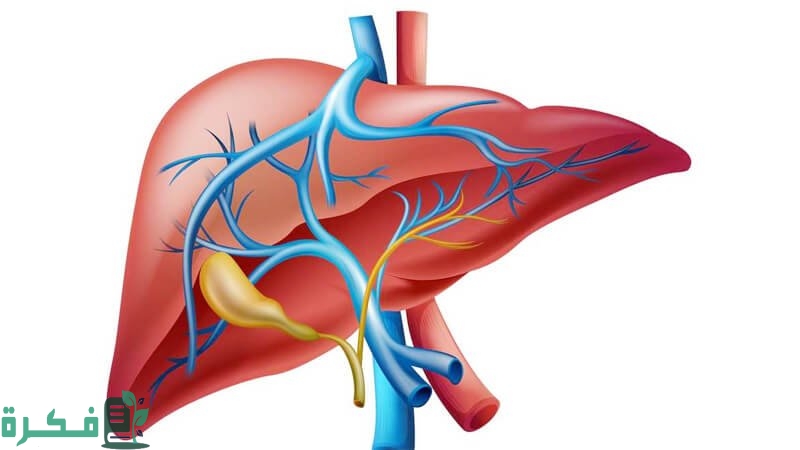

أكمل القراءة »كيف أعرف أن وظائف الكبد سليمة عبر موقع فكرة، الكبد هو عضو مسؤول عن طرد السميات من المستقلبات المختلفة في…